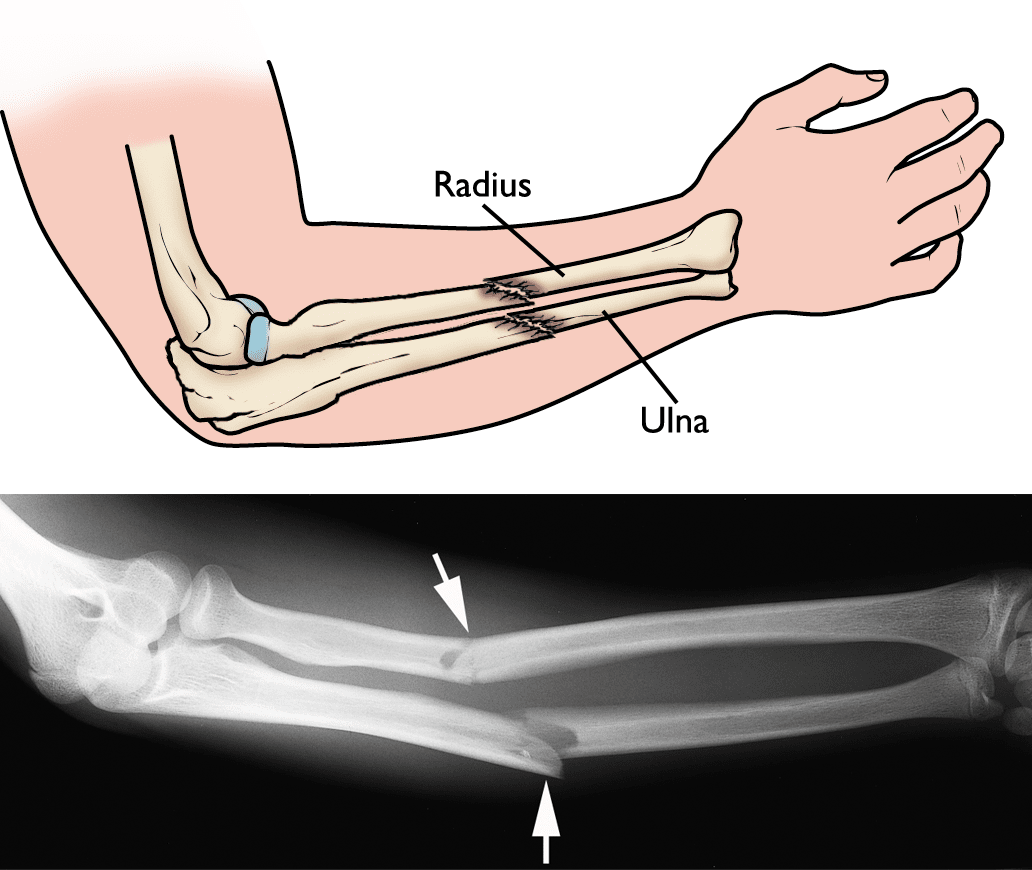

Fractured Ulna With Dislocation Of Radius Clipart Etc Images and